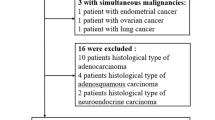

Patients with concurrent or previous malignancies, those lacking preoperative MRI assessments, patient who did not undergo surgery, and those with incomplete histological reports were excluded from the study.

From a database of 140 patients who underwent MRI examination between January 2015 and October 2023, a total of 68 patients with histologically proven locally advanced CC met the inclusion criteria and their MRI images were retrospectively reviewed. Seventy-two patients were excluded from our study due to missing data, incomplete preoperative MRI examination, or with disease progression (Fig. 4).